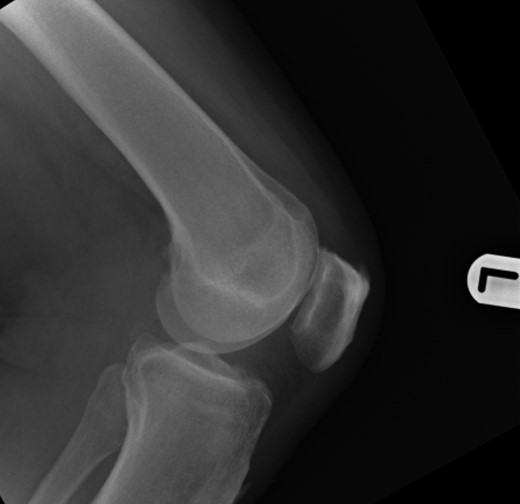

Nineteen months earlier the patient had consulted his general practitioner complaining of left knee pain. Radiographs performed at that time were reported to show joint space narrowing within the patello-femoral compartment as well as early joint space narrowing within the medial compartment. A subchondral lucency was also noted within the patella which was described as a subarticular cyst secondary to the previously mentioned patello-femoral degeneration (Figs 1–3).

The absence of associated features of systemic disease, as well as radiographic appearances in keeping with early patello-femoral osteoarthritis (OA), account for the delay in diagnosis. The initial images suggest mild degeneration but, whilst subarticular cysts are a radiographic feature of OA, the lesion shown in this case is larger than would be expected with the level of disease shown elsewhere in the joint.